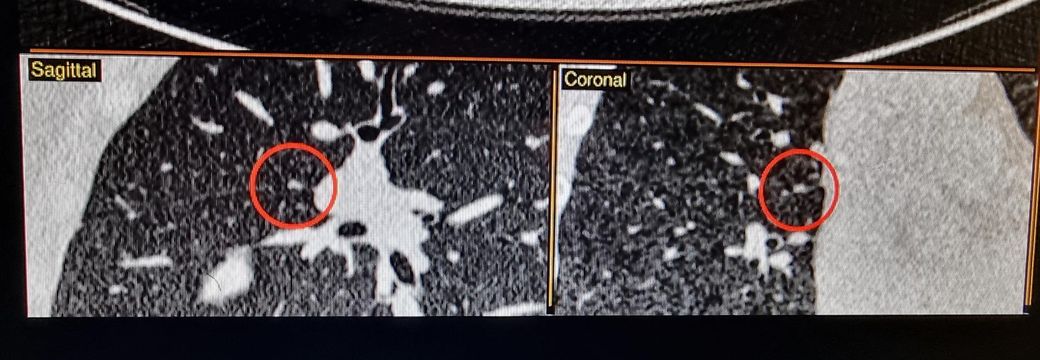

CT에서 환자분이 말씀하신 것처럼 작은 결절은 한 커트만으로는 알 수 없고 여러 커트를 봐야 합니다.

어찌되었던 이 사진만 보면 결절처럼 보이기는 합니다.

하지만 결절은 위아래 사진을 같이 확인을 해보셔야 합니다.

한 커트에만 나와있다면 약간 애매하다 할 수 있습니다.

말씀하시는 결절이 착오가 아니라고 하더라도 모양이나 크기로 봐서는 추적관찰을 하면 되는 것처럼 보입니다.